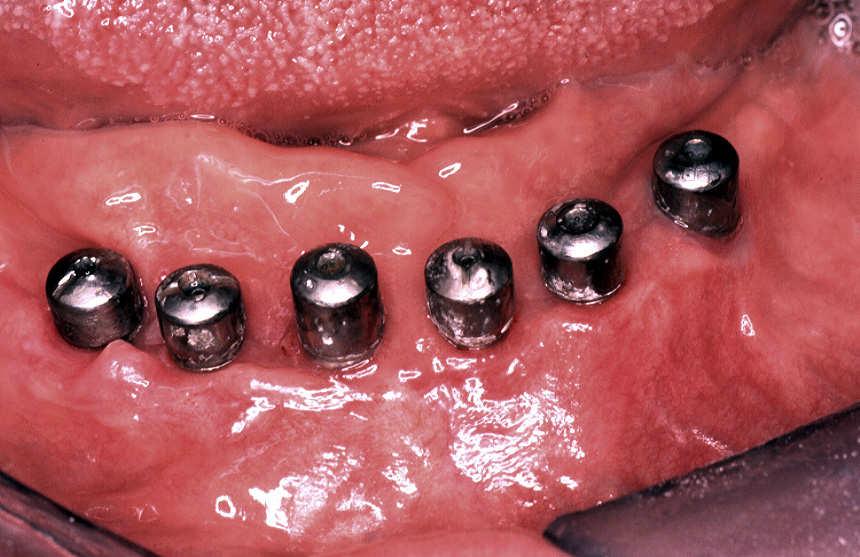

Patient, PCR positively for HPV categorizes. The papillomas are around of the titan implants, without prosthesis,

With help of a 810nm diodes lasers and a 400 micron fiber, 2.0 watts of performance with CW are removed all neoformation without locally Anestesie. There is sutures